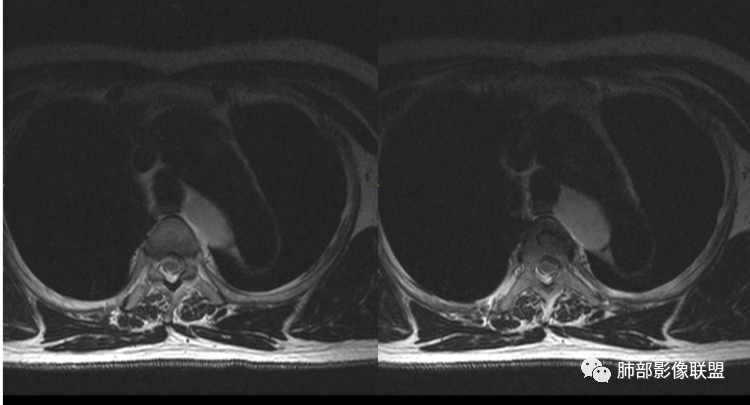

从MRI信号来看不支持单纯性囊肿,CT上看密度低强化无或者低而且柔软,上下径较长,考虑节细胞瘤可能大,和神经鞘瘤鉴别。

@诸暨市人民医院杨泽锋?我支持你诊断,病灶偏软,未见明显强化,T1信号不是很低,支持神经节细胞瘤。

磁共振上显示不是水的信号,考虑神经源性肿瘤。

男性,43岁,体检发现后纵隔占位,边缘光整,CT示密度均匀,周围组织受压移位,无钙化囊变及脂肪组织,增强未见明显强化。MRI:T1示肿块信号较肌肉高,T2不均匀高信号。考虑为良性病变,第一是神经节细胞瘤,其次是支气管源性囊肿。

中年男性,无症状,后纵隔肿块,长径大矢状位于横径,质地偏软,塑形,等t1稍长t2,比较均质,增强轻微强化,与脊柱,主动脉,食管脂肪间隙存在,部分层面与脊柱相贴,骨质无改变,周围无肿大淋巴结,考虑神经源性肿瘤,节细胞神经瘤可能大,鉴别心包斜窦,淋巴瘤,淋巴管囊肿。